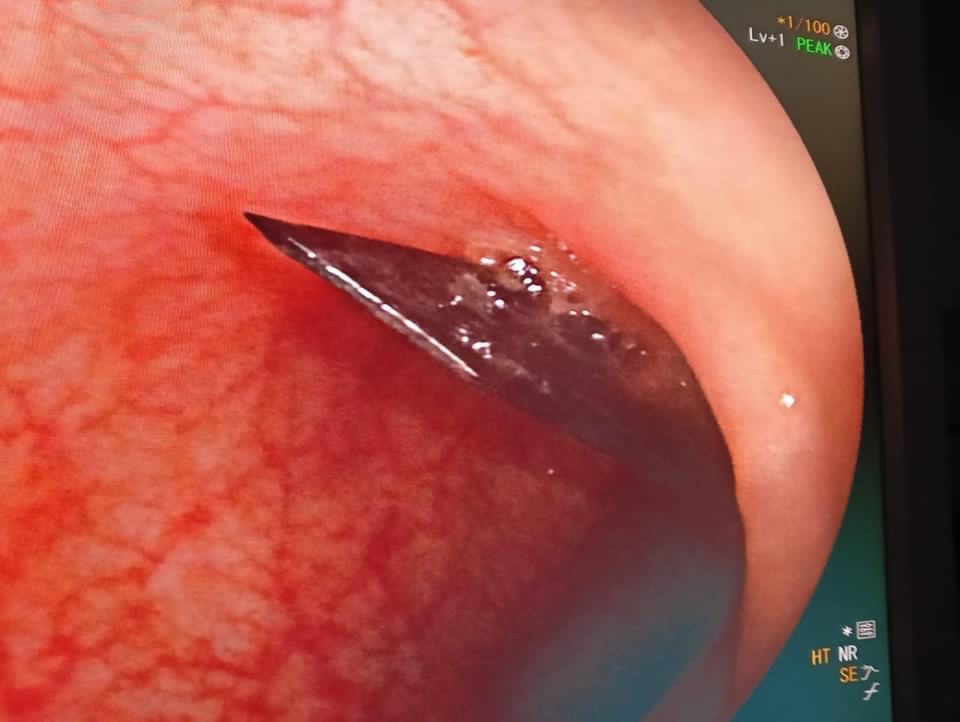

استخراج مشرط جراحي من داخل أمعاء فتاه بمستشفي المنصورة التخصصي

نجح فريق طبي بمستشفى المنصورة التخصصي التابعة لأمانة المراكز الطبية المتخصصة، من إجراء عملية نادرة بالمنظار الطبي لفتاة تعاني من اضطراب نفسي تبلغ من العمر 16 ابتلعت مشرط طبي، واستطاع فريق الجهاز الهضمي والمناظير بمستشفى المنصورة التخصصي، من استخراج المشرط الجراحي من داخل أمعائها باستخدام المنظار، ودون الحاجة إلى تدخل جراحي، والحالة بصحة جيدة وتم خروجها من المستشفى.